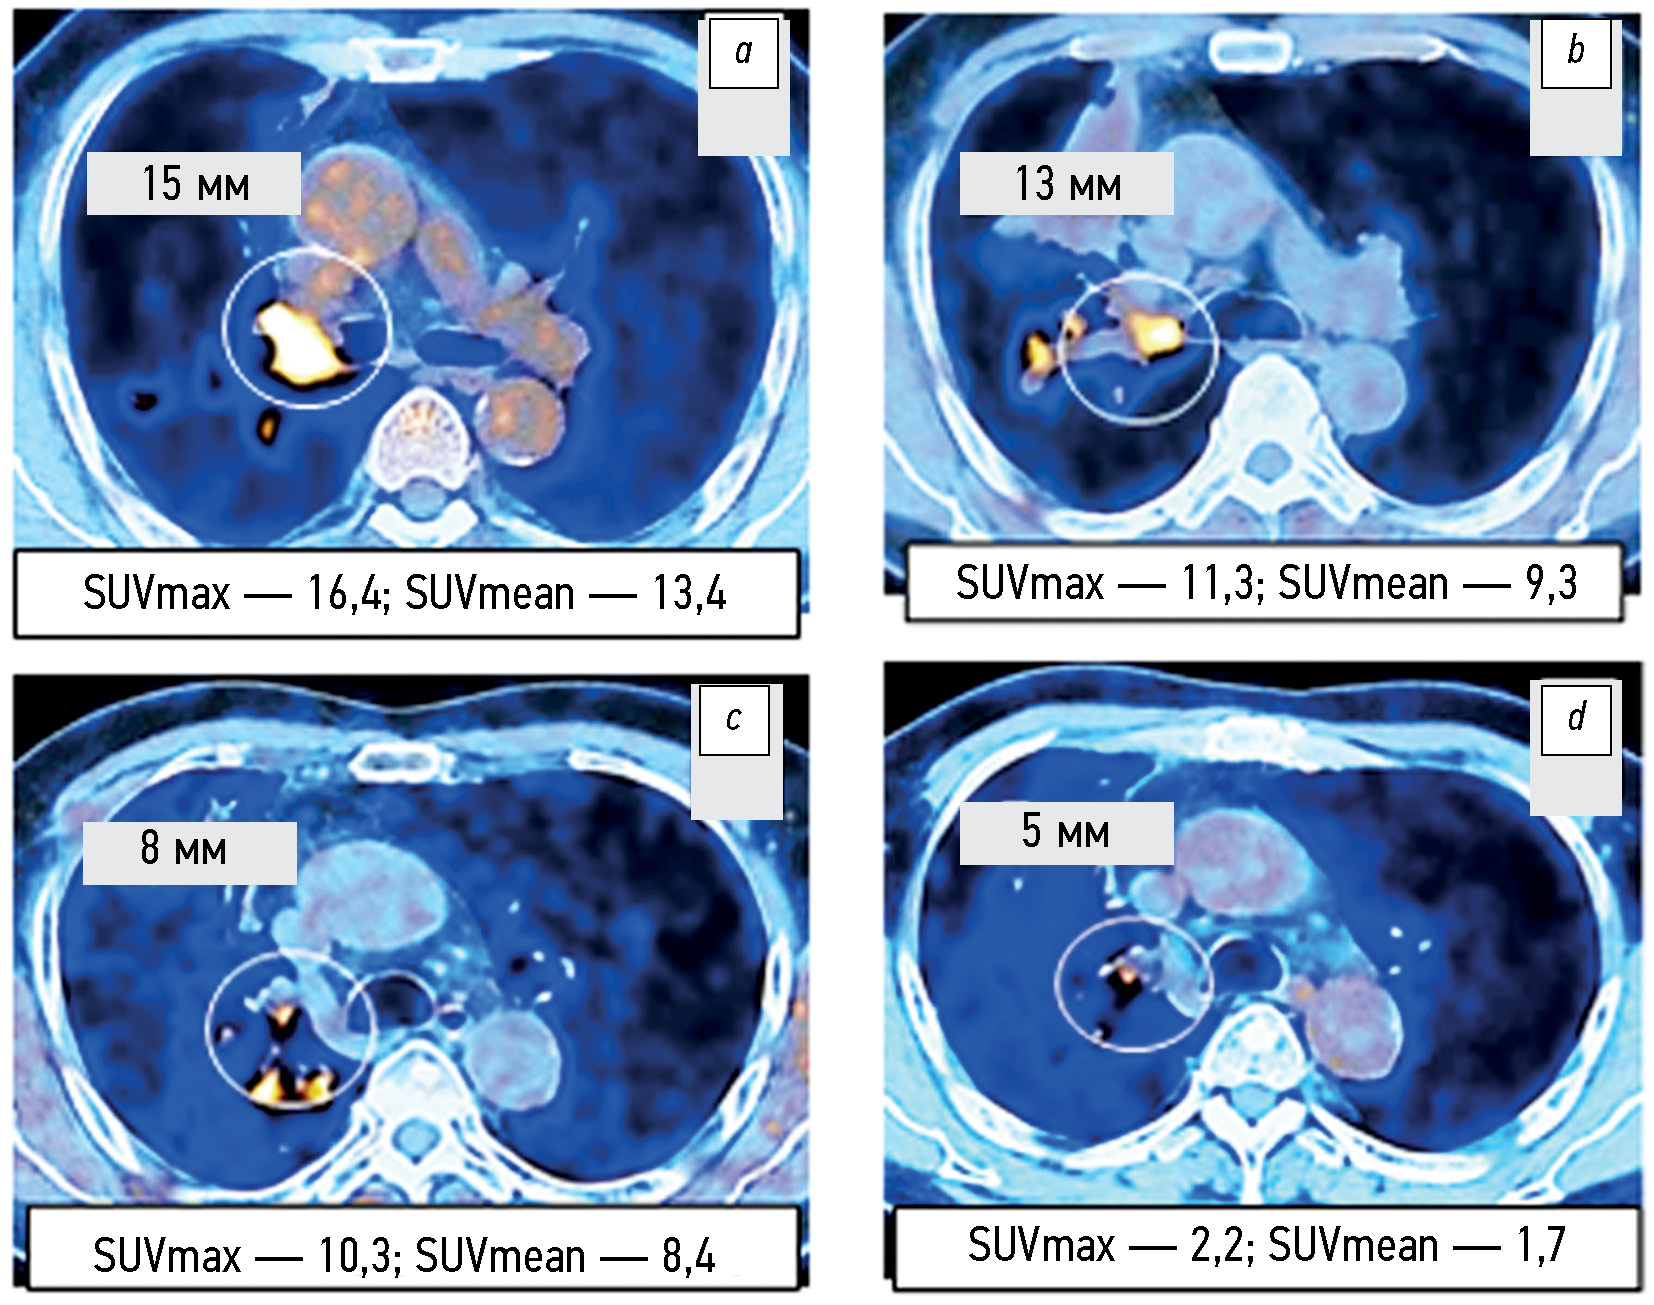

Capabilities of positron emission tomography/computed tomography in a comparative assessment of the effect of various targeted therapy options in patients with EGFR-mutated non-small-cell lung cancer

AIM: To explore the capabilities of positron emission tomography combined with computed tomography based on the RECIST 1.1 criteria and changes in SUVmax and SUVmean metabolic parameters for the comparative assessment of the tumor response to targeted monotherapy and combination therapy with tyrosine kinase inhibitors in patients with EGFR-mutant non-small cell lung cancer.

MATERIALS AND METHODS: The 2019–2022 examination records of positron emission tomography combined with computed tomography with 18F-fluorodeoxyglucose (18F-FDG) in 105 patients with non-small cell lung cancer were analyzed, including 75 patients with EGFR-activating mutation. The radiation exposure was adjusted individually and ranged from 45 to 90 mSv. The volume activity of the 18F-FDG radiopharmaceutical was 260–500 MBq. The change in the total largest diameters of the target lesions and SUVmax and SUVmean metabolic parameters were assessed before treatment initiation and 1.5–2.0 months after it. The follow-up duration for the changes in positron emission tomography combined with computed tomography findings in 17 patients with non-small cell lung cancer was at least 12 months.

RESULTS: According to positron emission tomography combined with computed tomography images and SUVmax and SUVmean changes, disease progression was significantly less common (p = 0.043 and p =0.029) in patients with EGFR-mutant non-small cell lung cancer from Groups 2 and 3 who received combination therapy with tyrosine kinase inhibitors and bevacizumab or chemotherapy than in Group 1 and control group (4.2% vs. 20.0%–21.8%). An insignificant trend (p =0.092) to a higher partial response to therapy (58.3% vs. 40.0%) was noted. Similar changes in the total largest diameters of the target lesions at the early stage of therapy appeared to be not significant (p =0.187). Within the long-term follow-up of some patients with non-small cell lung cancer, in at least 50% of cases, changes in the total largest lesion diameters are consistent with the relevant SUVmax and SUVmean alterations found in the first control study.

CONCLUSIONS: Based on the positron emission tomography combined with computed tomography data and alterations in SUVmax and SUVmean metabolic parameters, the early tumor response to combined therapy with tyrosine kinase inhibitors and bevacizumab or chemotherapy compared with targeted monotherapy with tyrosine kinase inhibitors or chemotherapy of the control group was characterized by a significantly lower rate of metabolic disease progression, although a similar tendency of the change in the total largest diameters of target lesions according to RECIST 1.1. was not significant. Changes in SUVmax and SUVmean metabolic parameters at the early stage of therapy are at least 50% faster than similar changes in the total largest diameters of the target lesions, which can be used for the timely identification of patients with a high risk of further progression as determined by RECIST 1.1.